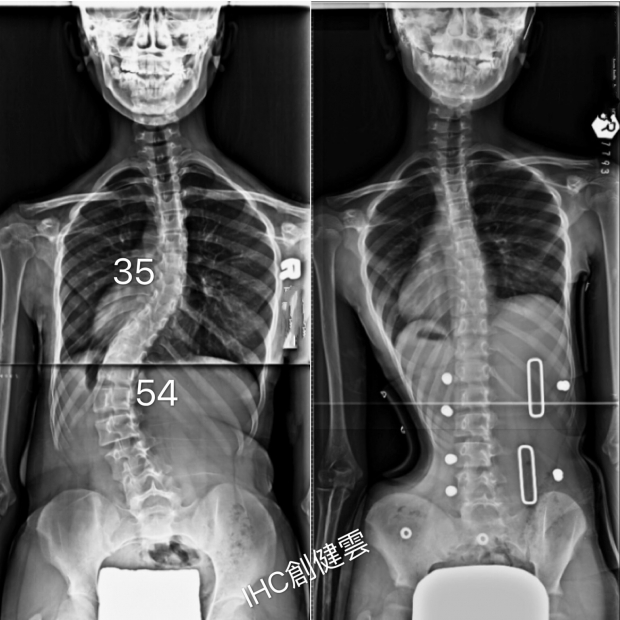

胸彎35度,腰彎54度

14歲重度脊椎側彎女孩